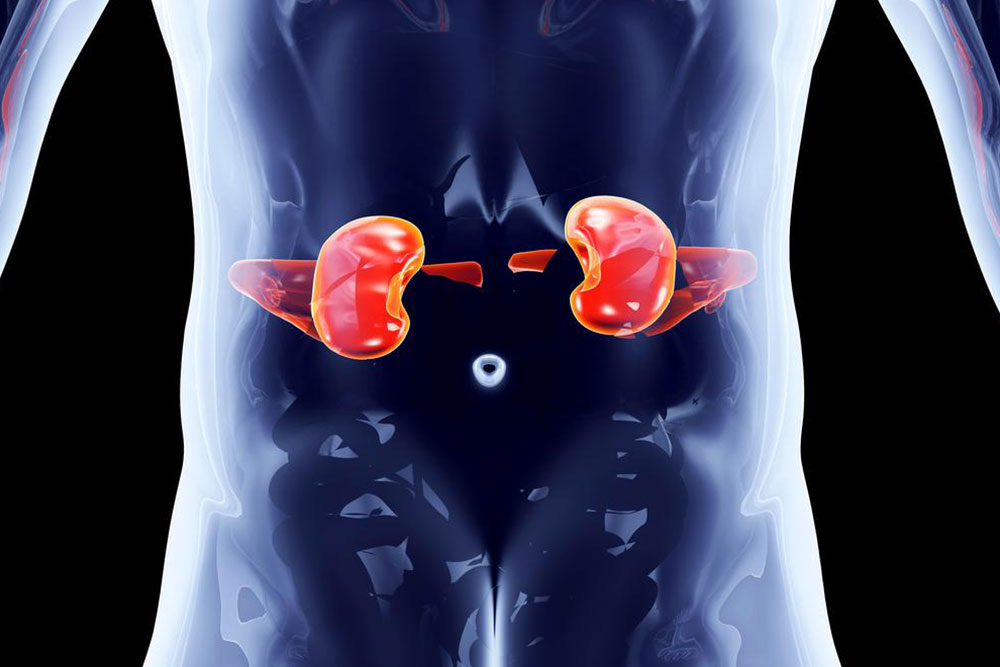

Kidney disorders are something that plagues a majority of the population. Contrary to popular belief that you can only undergo treatment for kidney disorders and cannot prevent it, there are some popular preventive measures which would hold your kidney disorders at bay.

Here are some preventive measures that would help prevent kidney disorders in the long run.